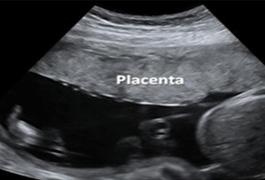

La ecografía del III trimestre (30-34 semanas) valora el crecimiento fetal (talla y peso), la localización de la placenta y el volumen del líquido amniótico.

Figura 37. Ecografía de II trimestre Defectos de tubo neural (signo de cabeza de limón) Figura 38. Ecografía de III trimestre Localización de la placenta